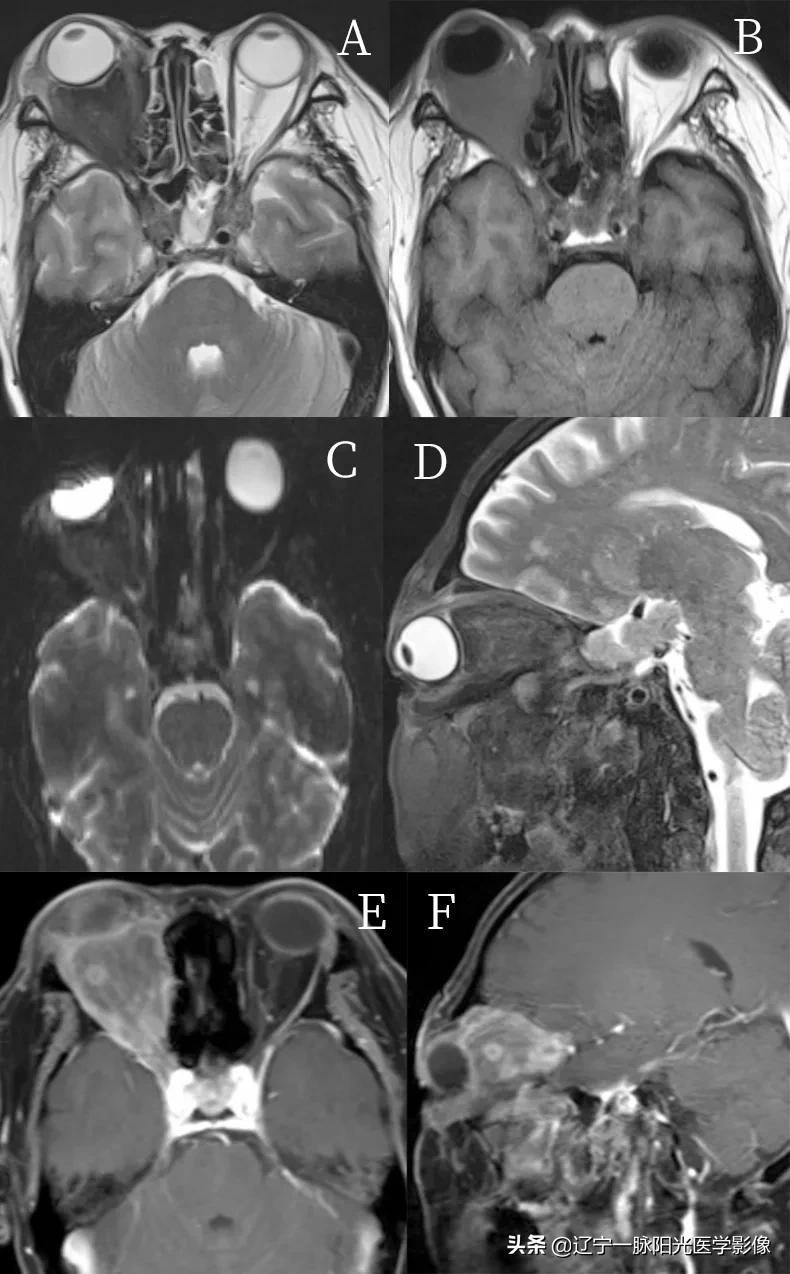

图 A、B 轴位示右侧眼球稍向前突,球后充盈团块状软组织信号影,范围约 4.3 cm×3.5 cm, T1WI、T2WI 呈低信号

图 C 示 DWI 亦呈低信号

图 E、F 增强后呈不均匀明显强化,其内见环行强化,病灶包绕右侧视神经及眼肌

病理诊断:炎性假瘤

肌炎型炎性假瘤可累及一条眼外肌或多条眼外肌,一侧眼眶或双侧眼眶受累均可见到,眼外肌肿大严重时可呈球形,轴位扫描时上直肌和下直肌的斜切面容易误认为肿瘤,此时冠状扫描像可以帮助确诊。MRI 像上以淋巴细胞浸润为主的炎性假瘤病变在 T1WI 显示为中信号,T2WI 为高于或等于脂肪的信号强度

纤维硬化型炎性假瘤由于胶原纤维成分多则病变在 T1WI 和 T2WI 均显示为低信号

肌炎型肿大的眼外肌 T1WI 为中信号强度,T2WI 为中等或偏高信号强度